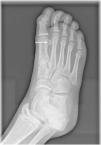

Presentamos el caso de un varón de 13 años, que acudió a urgencias por dolor en la región de la articulación metatarsofalángica del primer dedo del pie derecho tras golpear accidentalmente el suelo jugando un partido de fútbol el día anterior. Presentaba leve tumefacción en hallux y dolor a la palpación en dicha articulación. En la radiografía de pie (ver fig. 1) se observó la presencia de un hueso sesamoideo lateral partido.

Los sesamoideos son pequeños huesos redondeados localizados en los tendones para reforzar y disminuir el estrés ejercido sobre ellos1. En los pies distinguimos el sesamoideo lateral y el medial, ambos localizados en la superficie plantar de la cabeza del primer metatarso2. El sesamoideo bipartito es una variante de la normalidad, resultado de la fusión incompleta durante el desarrollo, con una incidencia de entre el 7-30%1. Su principal diagnóstico diferencial es la fractura de sesamoideo, que generalmente se produce por un mecanismo de hiperextensión forzada del primer dedo, y que en ocasiones puede pasar desapercibida derivando en complicaciones como necrosis avasculares2,3. Nuestro paciente siguió un tratamiento conservador, con reposo físico y descarga plantar. Evolucionó favorablemente y en un plazo de menos de 2 semanas reinició progresivamente su actividad deportiva.